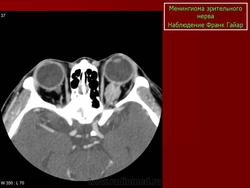

Наиболее типичная черта: объемное образование, расположенное вдоль интраорбитальной части зрительного нерва, накапливающее КВ и содержащее обызвествления по типу трамвайных рельс. Форма: тубулярная (65%) > на ножке (25%) > веретеновидная (10%). Формируется вокруг нерва, реже растет эксцентрично или имеет ножку

КТ-семиотика

На КТ срезах без контрастного усиления менингиома зрительного нерва выглядит изоденсной. Типично наличие линейных или точечных обызвествлений. Симптом «трамвайных рельс» отражает накопление КВ по сторонам гиподенсного зрительного нерва или наличие обызвествлений в структуре опухоли. Как правило, наиболее дистальная часть зрительного нерва, в месте его вхождения в глазное яблоко, не содержит обызвествлений.